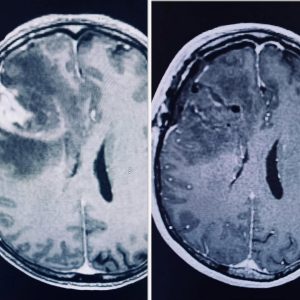

Gleolan is a visual imaging contrast agent that is used to help map out and define high-grade primary brain tumors like Glioblastoma for surgical removal. This exciting new method allows neurosurgeons to remove tumor cells more precisely, and more safely than ever before.

Surgical treatment of Glioblastoma can present a considerable challenge since the tumors often have “finger-like” projections that spread into different parts of the brain and can be hard to fully remove. Gleolan helps highlight these tumors in detail so that complete tumor removal can be more easily achieved.

Prior to surgery, patients drink the Gleolan contrasting agent which allows the surgical team to visualize the tumor in vivid contrast to distinguish it from the surrounding unaffected brain tissue. Under a special blue light microscope, the tumor turns bright pink or magenta—helping the surgeon to more safely and accurately remove all or most of the tumor from the brain.